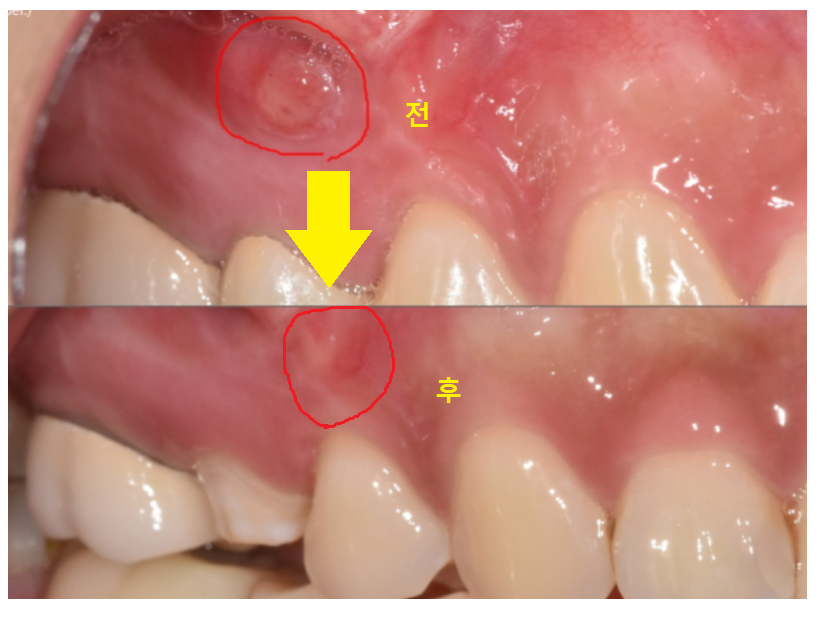

육안으로 보기에는 물집 잡힌 것처럼

잇몸이 볼록하게 부풀어 올라와 있었습니다.

염증이 잇몸 밖으로 빠져나온 것이죠.

한장으로 전후 차이 보여드릴께요~

잇몸에 볼록하게 물집처럼

잡혔던 염증도 사라졌죠~?